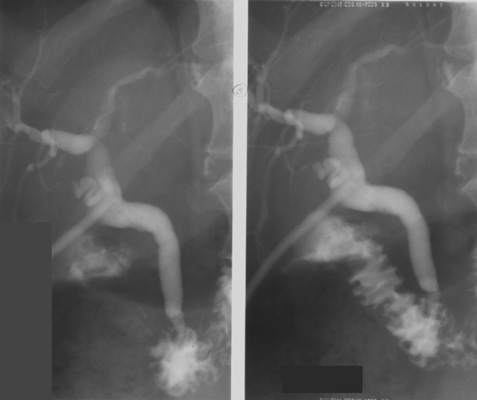

- Rotate the patient into a RPO position. After filling the

intrahepatic and extrahepatic ducts well with the contrast agent, take a

final image. Try to time the exposure for when contrast squirts from the

common bile duct (CBD) into the duodenum.